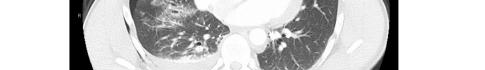

This leads me to the patient’s imaging, which is often key to reaching a final diagnosis in patients presenting with hemoptysis. As noted earlier, advanced imaging such as computed tomography (CT) is only possible once the patient has been sufficiently stabilized. Therefore, many physicians may have to initially rely on a portable chest radiograph (CXR) alone. A CXR is a bit of a mixed bag, with widely variable rates of diagnostic ability reported in the literature. Sometimes it can identify a localizing lung lesion such as a tumor or cavitation, or potentially a more diffuse process such as pneumonia or diffuse alveolar hemorrhage. This patient’s CXR fits more in the latter category with diffuse bilateral airspace disease and air bronchograms. It is fortunate that he was also able to receive a CT angiography (CTA), as this is often the ideal imaging study to identify the cause of bleeding in hemoptysis, especially if it is from a culprit lesion. As most cases of massive hemoptysis are from the bronchial arterial system, it is worth noting that this CTA should ideally be protocoled differently from the traditional pulmonary artery CTA used when evaluating for pulmonary embolism.1 This patient’s post-intubation CTA demonstrated widespread ground-glass opacities with prominent septal lines, dependent consolidation, and air bronchograms in the bilateral lung bases suggestive of diffuse alveolar hemorrhage and hemorrhagic pneumonia.

Image 2. Portable chest radiograph of a 44-year-old man with hemoptysis and hypoxemic respiratory failure showing diffuse bilateral coalescent airspace opacities with air bronchograms (black arrows). Table 2. Laboratory studies to consider in the work-up of massive hemoptysis.